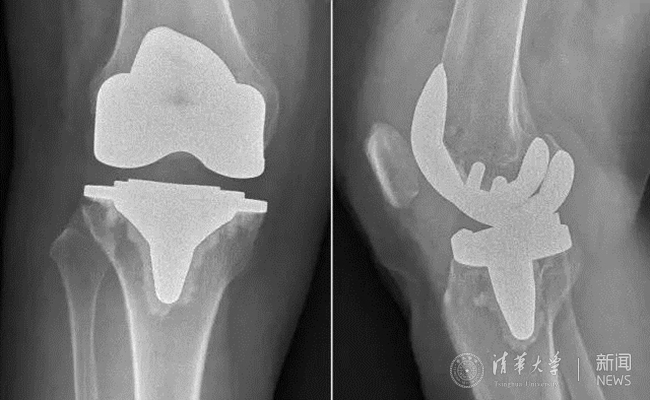

患者术后膝关节平片。

疗效改善的同时,新型假体对手术精准度的要求也提高了,为此,蔡谞教授和关节中心团队做了充足的准备,术前对手术参与人员进行了严格的操作训练。手术全程1个小时左右顺利结束,术后影像显示,新型假体安放位置精确,患者术后第2天即开始下床进行功能锻炼,术后7天顺利出院。